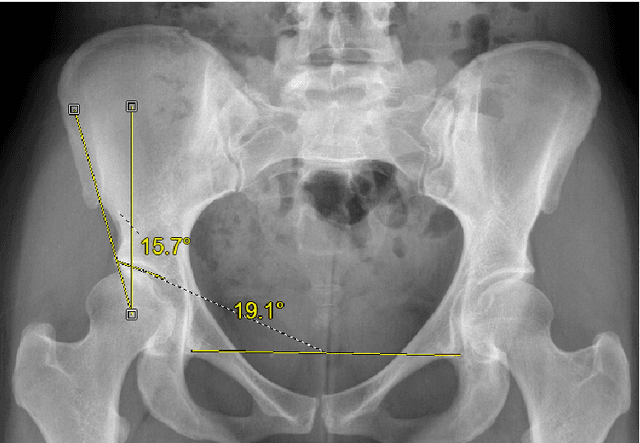

Abstract:Dysplasia is a recognised risk factor for osteoarthritis (OA) of the hip, early diagnosis of dysplasia is important to provide opportunities for surgical interventions aimed at reducing the risk of hip OA. We have developed a pipeline for semi-automated classification of dysplasia using volumetric CT scans of patients' hips and a minimal set of clinically annotated landmarks, combining the framework of the Gaussian Process Latent Variable Model with diffeomorphism to create a statistical shape model, which we termed the Gaussian Process Diffeomorphic Statistical Shape Model (GPDSSM). We used 192 CT scans, 100 for model training and 92 for testing. The GPDSSM effectively distinguishes dysplastic samples from controls while also highlighting regions of the underlying surface that show dysplastic variations. As well as improving classification accuracy compared to angle-based methods (AUC 96.2% vs 91.2%), the GPDSSM can save time for clinicians by removing the need to manually measure angles and interpreting 2D scans for possible markers of dysplasia.